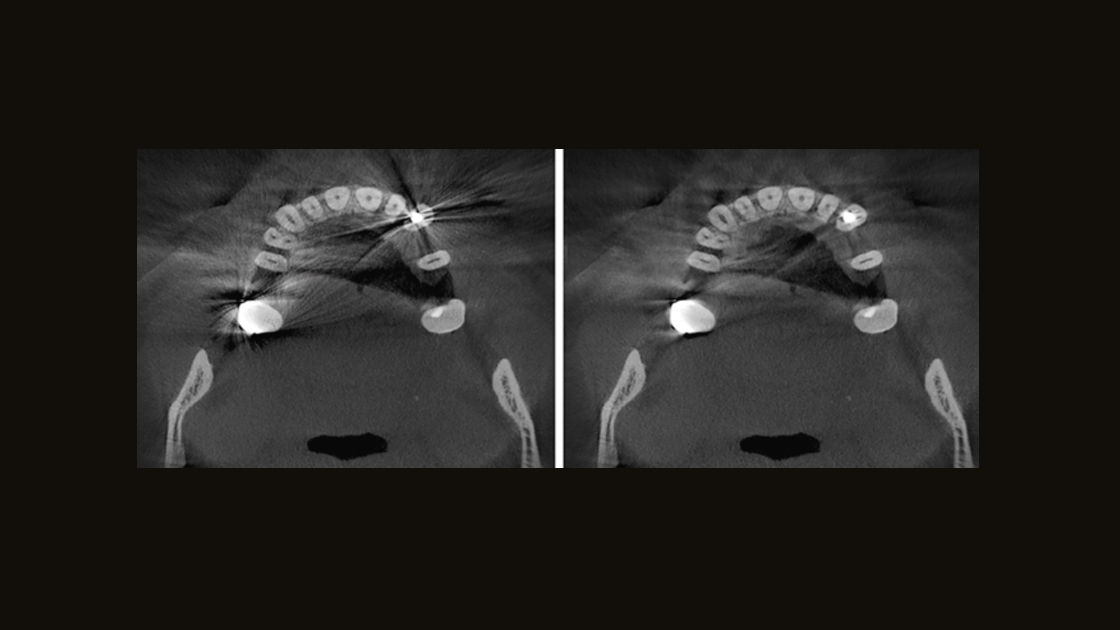

Verbeter de mondgezondheid van uw patiënten door de mogelijkheid te hebben om een diagnose te stellen en behandeling te plannen voor vrijwel alle etiologie in de dentomaxillofaciale regio. DS-röntgenoplossingen ondersteunen de behoeften van de patiënt, van vastlegging van de temporomandibulaire gewrichten tot visualisering van de kleinste details met behulp van endodontische röntgenfoto's met een hoge resolutie van maximaal 80 μm.

Betrouwbare beoordeling mogelijk gemaakt door precisie

Elke behandeling begint met een nauwkeurige diagnose